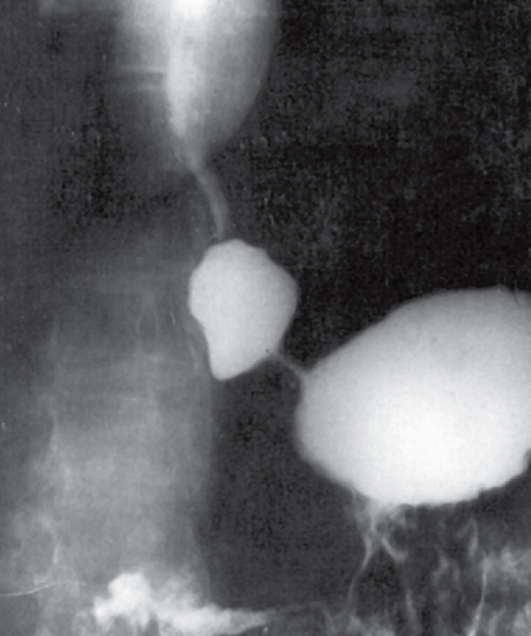

Рис. 28.Рентгенограмма пищевода больной, 49 лет